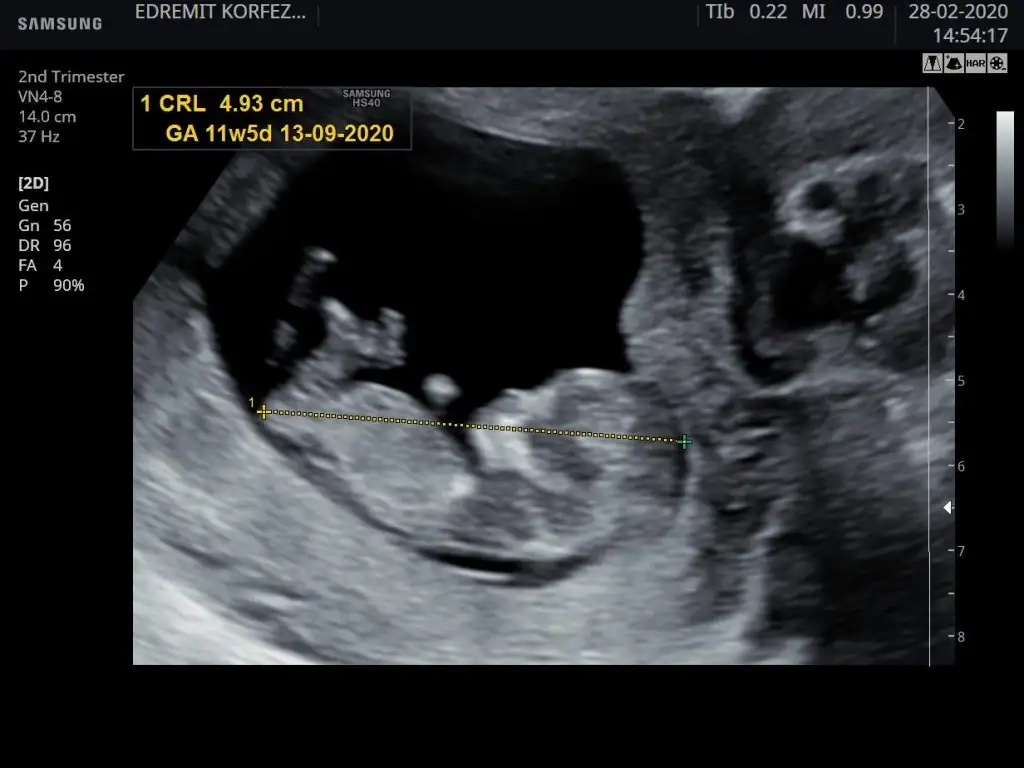

Malesef bir tek bu var 11+5 olarak başka yok11 12 13 haftalar nub için uygun şimdilik sanki erkek gibi gibi dediğimiz usgleri paylaşırmısınız

Şuan 19 haftalık kordon dolandığı için göremedi doktor cinsiyeti11 12 13 haftalar nub için uygun şimdilik sanki erkek gibi gibi dediğimiz usgleri paylaşırmısınız

Net değil usgMalesef bir tek bu var 11+5 olarak başka yok![]()